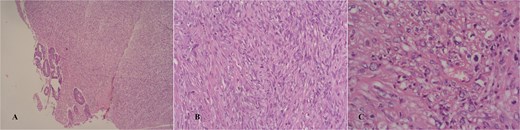

Macroscopically, the lesion measured 4.5 × 3.5 cm and partially encircled the anterior rectal wall (Fig. 2). Histologically, the tumor was composed of malignant mesenchymal cells arranged in a dense, solid pattern. Most of the cells exhibited a spindle-shaped morphology (Fig. 3A–C), and scattered bizarre multinucleated cells were also observed. Mitotic activity was high, with up to 30 mitoses per 10 high-power fields. The tumor demonstrated extensive invasion through all rectal wall layers and had infiltrated the surrounding soft tissue.

Hematoxylin/eosin stain showing an infiltrative spindle cell neoplasm sparing the mucosa in a glance (A and B), high power field showing mild nuclear pleomorphism (C).